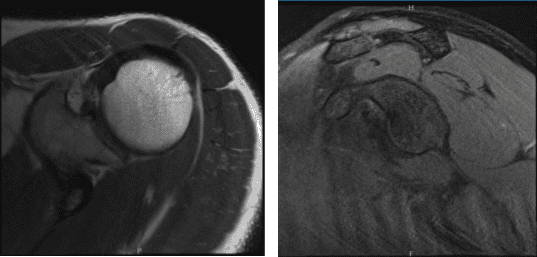

MRI-3T Left Shoulder Non-contrast

Left shoulder X Ray were presented and discussed and showed normal left shoulder radiographs. Recommended patient to undergo MRI to see the reason behind the pain. Found that there is very minimal AC joint osteoarthritis. No subacromial enthesophyte is visualized. Also noticed, mild rotator cuff tendinosis.